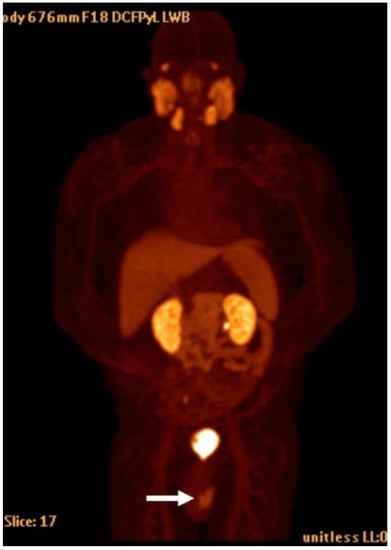

1.7. Fluorine-18 DCFPyL

Detection of Loco-Regional Disease and Distant Metastases